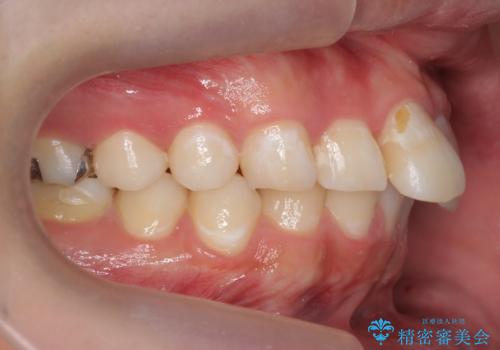

出っ歯が気になる 歯をぬかずに治療

- 前歯が出ているのを気にして来院。

左のかみ合わせが1本分ずれていましたが、機能的には問題ないのでそのまま変えずに治療しています。

ずれている分を、上の歯を1本抜くか(ワイヤー矯正になります)、右上の奥歯を1本分後ろに送るか、そのまま前歯を並べるのかを選んでいただきました。

右のかみ合わせをそのままに、最小限の動かし方で見た目を改善しました。